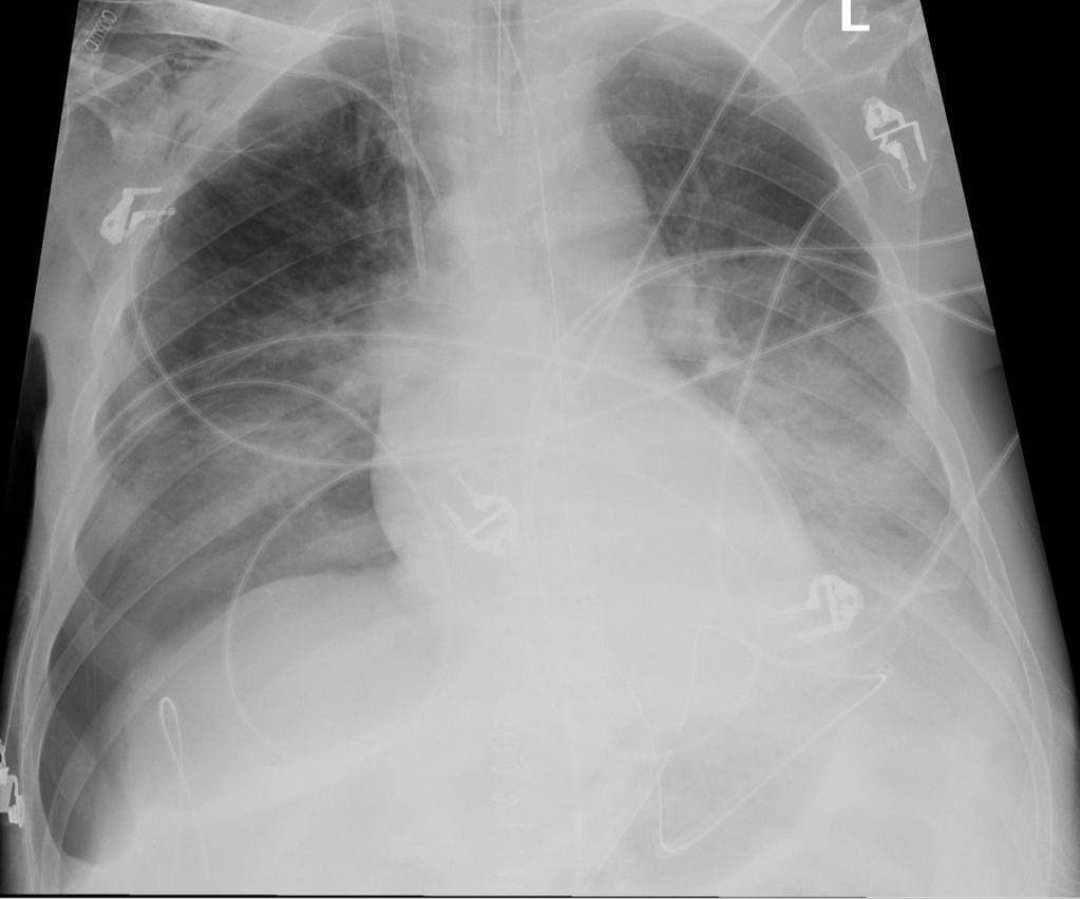

Diagnosis

Giant compressive emphysema

👉 the chest X-ray at the patient's bed showed an alveolar syndrome of the right lung (arrow: right/up)

👉with right deviation of the mediastinum (arrow: right/down)

👉 clarity of the right lung except at the apex (arrow: left)